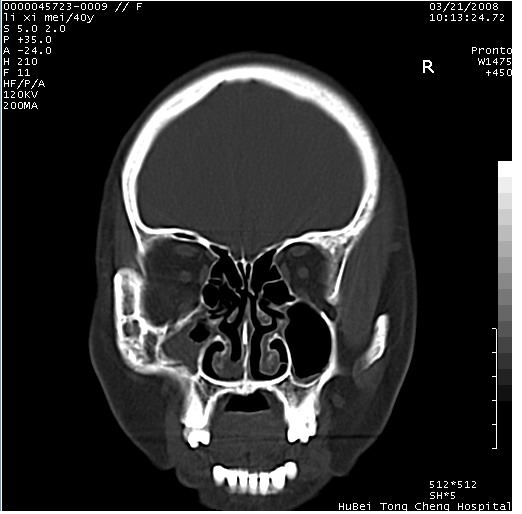

以下是引用卜一在2008-3-21 20:18:00的发言:[br]双侧上颌窦炎症,双下鼻甲肥大!不除外霉菌感染!

以下是引用qiuleiyu在2008-3-21 21:46:00的发言:[br]支持;上颌窦炎,窦内高密度影,建议横断位观察与上颌窦前壁关系。除外骨源性病变。